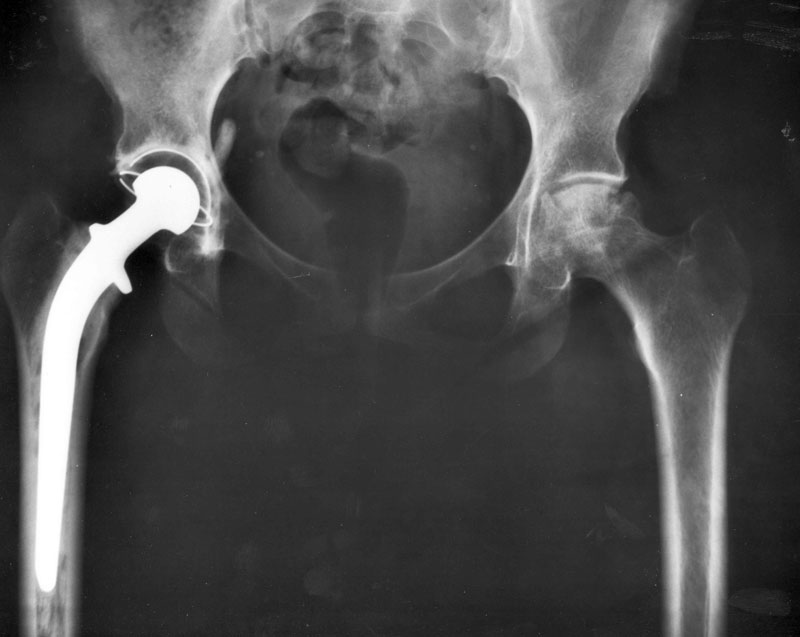

An X-Ray showing hip replacements